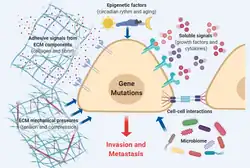

Facteurs entrant en jeu

Le phénomène de métastase est une série complexe d’étapes au cours desquelles des cellules cancéreuses quittent le site originel (tumeur primaire) et migrent vers d'autres parties du corps en utilisant le système lymphatique et/ou le système sanguin. Pour ce faire, des cellules malignes se séparent de la tumeur primaire et s’attachent en les dégradant aux protéines qui composent la matrice extracellulaire (ECM), laquelle sépare la tumeur des tissus voisins. En dégradant ces protéines, les cellules cancéreuses sont capables de briser l'ECM et de s’évader. Quand des formations cancéreuses orales métastasent, elles voyagent généralement par le système lymphatique vers les ganglions lymphatiques du cou. On dit alors que le cancer est « métastasé ».

Modification de la matrice extracellulaire

La matrice extracellulaire est un échafaudage de macromolécules interconnectées formant un réseau qui englobe les cellules présentes dans les tissus et les organes[56]. Cette environnement spécialisé modifie les propriétés des cellules et affecte leur propension à proliférer, à migrer et à survivre[57],[58]. À la suite de déclencheurs physiologiques et pathologiques, la protéolyse partielles des macromolécules libèrent des peptides , appelées matrikines, sont libérées pour remodeler la matrice extra-cellulaire, rétablir un maillage fonctionnel et maintenir l'homéostasie des tissus[58],[59]. Dans les métastases cancéreuses, le remodelage de la matrice extra-cellulaire est détourné, conduisant à une tumorigenèse stromale[60],[61],[62],[63]. Une variété de composants majeurs de la matrice extra-cellulaire, comme les protéoglycanes, le collagène, les laminines, la fibronectine, l'élastine, d'autres glycoprotéines et les protéinases, sont impliqués dans les processus invasifs et métastatiques des cellules cancéreuses.

Facteur épigénétique

Microbiote